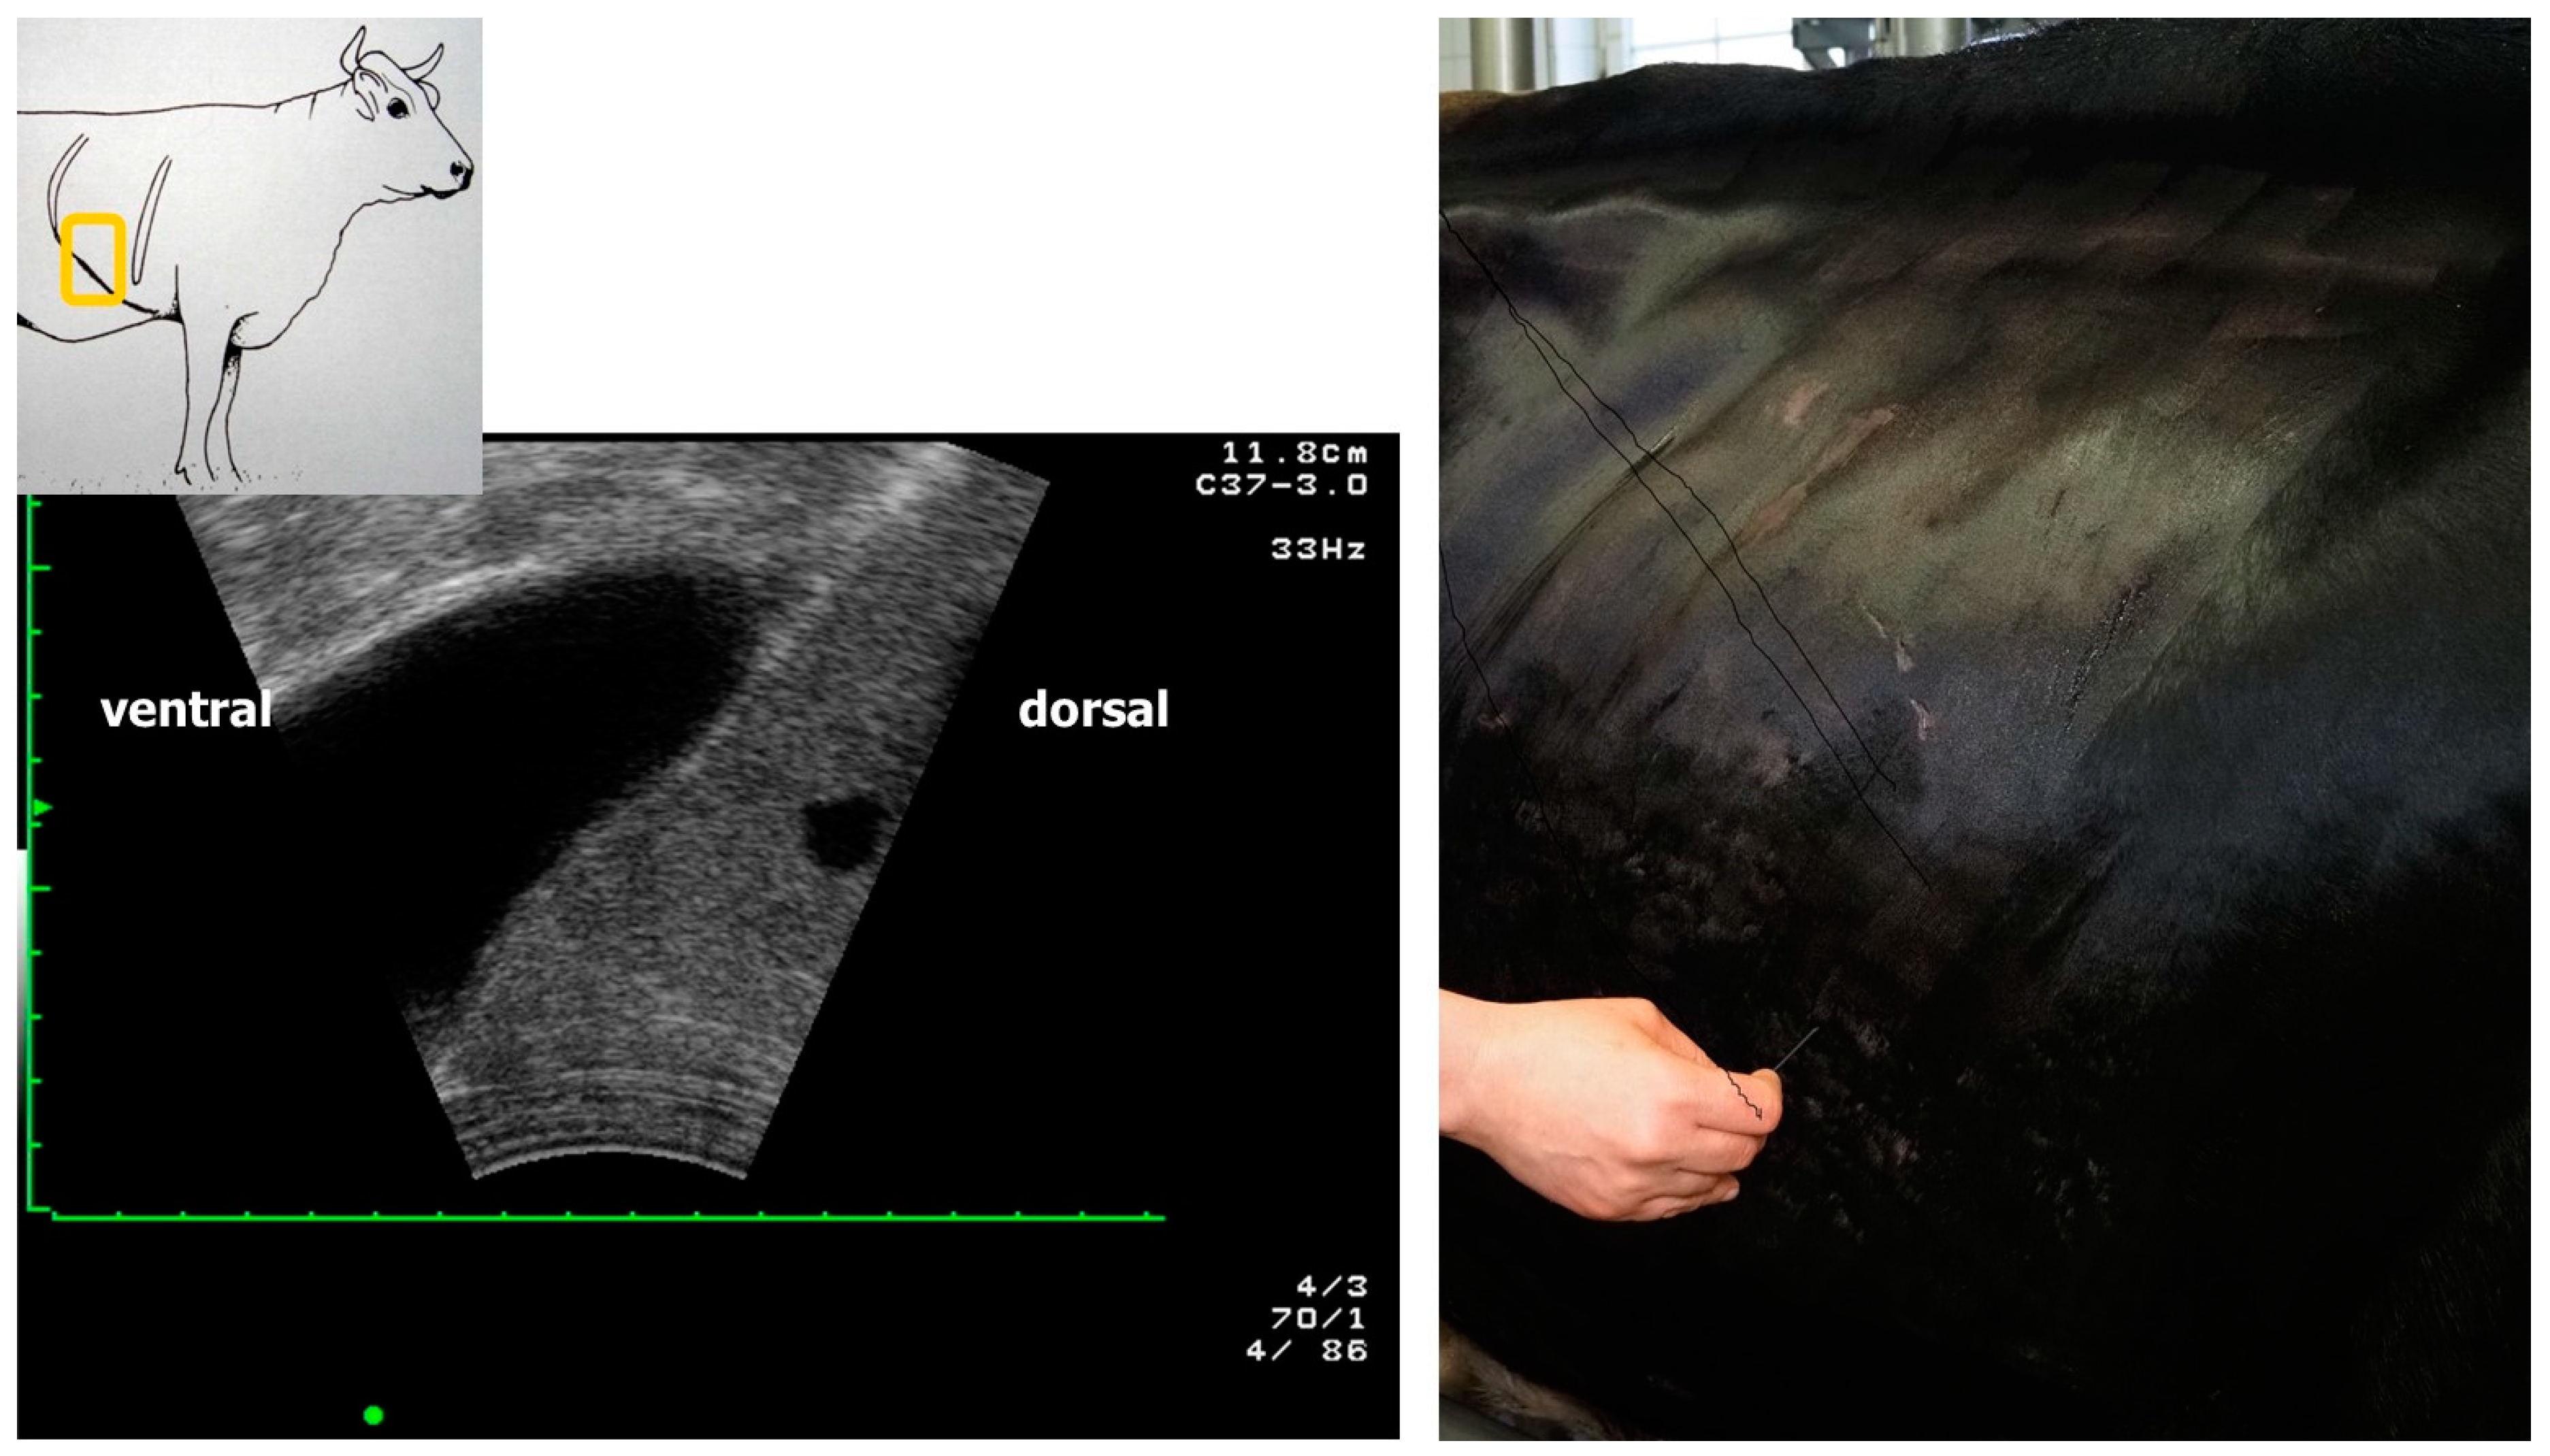

2.1. Description of Data

2.1.1. Data for the Derivation of Prediction Equations and Internal Validation

2.1.2. Data for External Validation